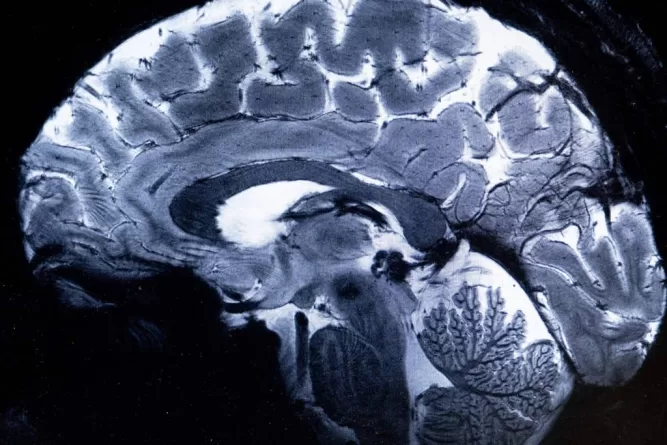

Uma limitação do estudo é que ele não mede os mecanismos cerebrais subjacentes que causam o aprimoramento da memória. Lin diz que uma teoria conhecida entre neurocientistas que estudam animais é que “memórias fracas podem ser ‘marcadas’ e posteriormente estabilizadas se forem seguidas por um evento saliente no que é conhecido como ‘marcação comportamental'”. Embora ele tenha dito que suas descobertas se alinham com essa teoria, ele espera usar imagens cerebrais e outras ferramentas no futuro para “observar os mecanismos cerebrais se desenrolarem em tempo real”.